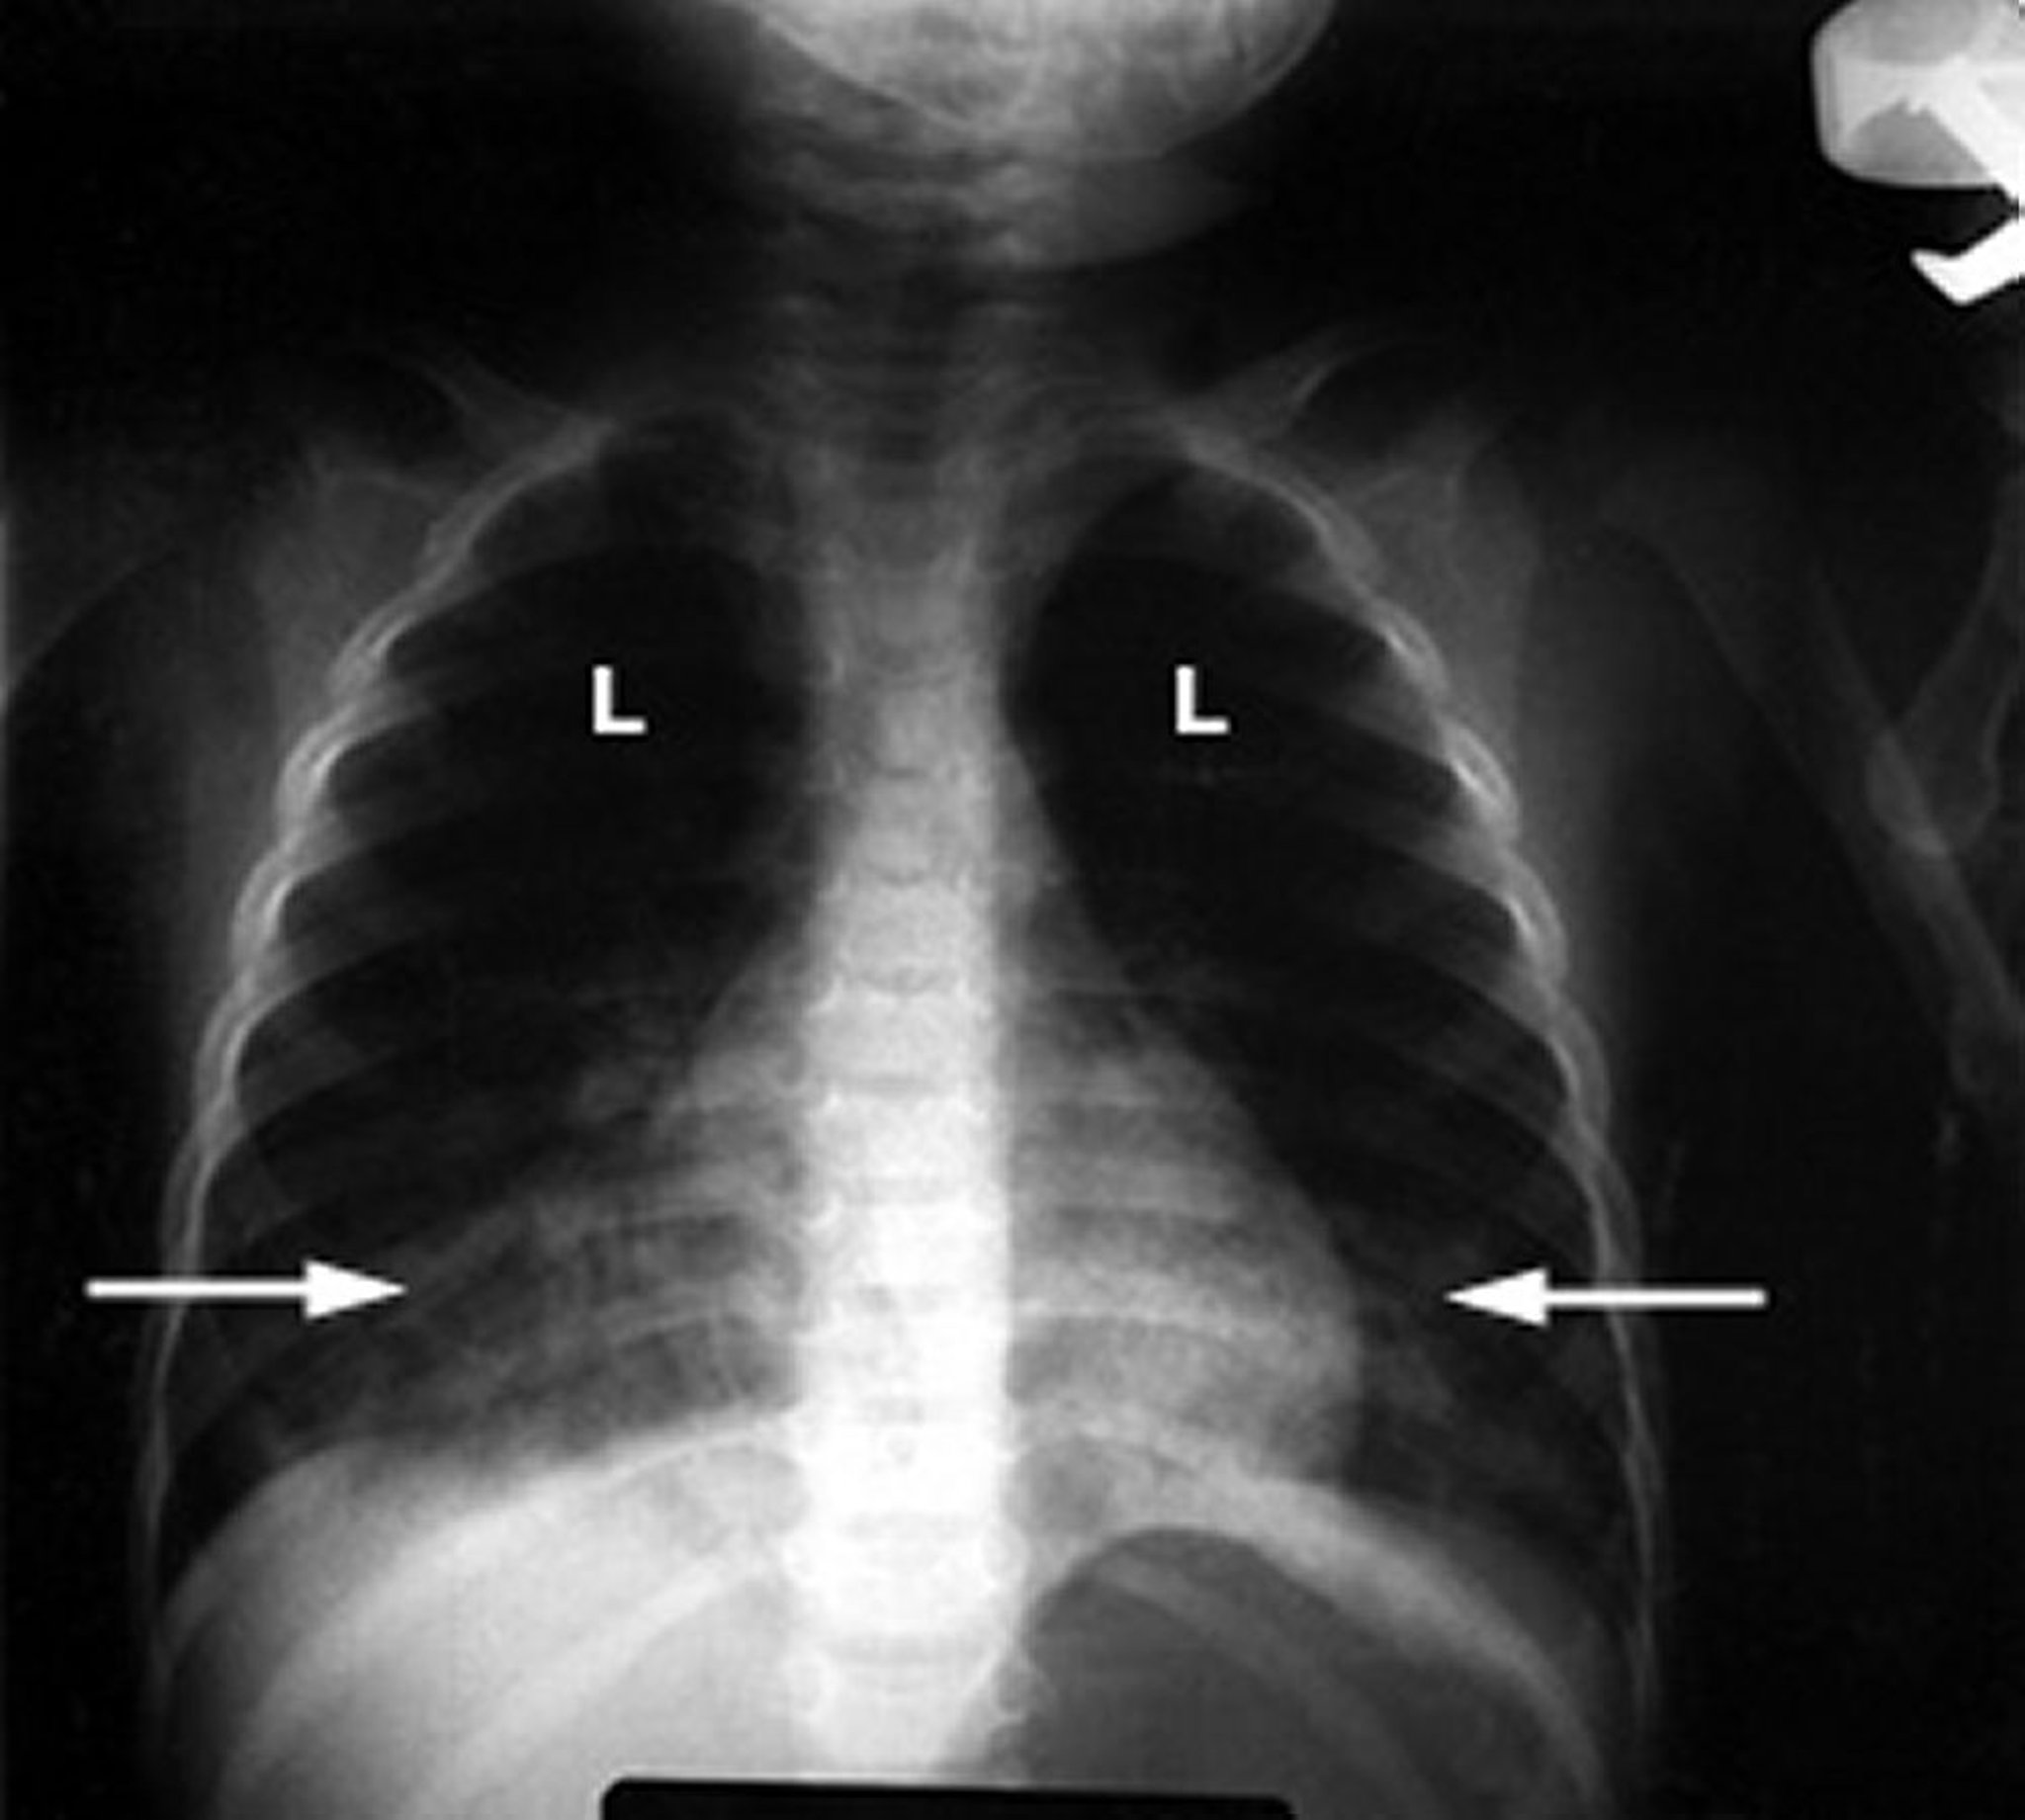

Neumonitis química causada por inhalación de hidrocarburos

Una radiografía de tórax anormal de un bebé muestra infiltrados blancos y esponjosos (flechas) en los pulmones (L), lo que indica inflamación. Este hallazgo es característico del daño pulmonar debido a la intoxicación por hidrocarburos.

Cortesía de G. Schmidt, MD.